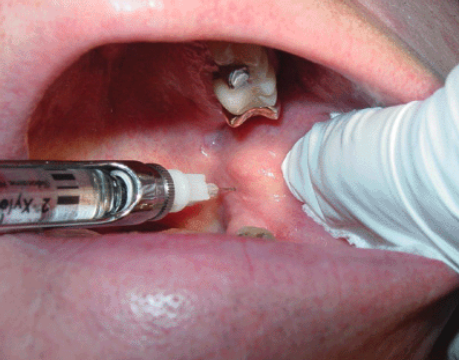

what nerve block is indicated when mandibular posterior buccal soft tissue is required for dental procedure?

long buccal nerve block

what is a contraindication for long buccal nerve block?

infection/acute inflammation

what areas are anesthetized with long buccal nerve block?

Soft tissue and periosteum buccal to the mandibular molar teeth

target area of which nerve block?

what is the proper injection site for long buccal nerve block?

buccal side of 2nd or 3rd molar (injection depth is very shallow)